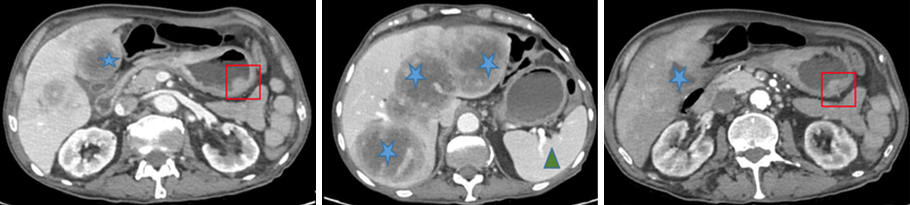

Voici ce que vous observez lors de la gastroscopie.

Figure 1 (Élisabeth Capelle, La Revue du Praticien)

Question 4 - Sur ces images vous pouvez observer (une ou plusieurs réponses exactes) :

Absence d’ulcère visible sur cet examen. Un ulcère est une perte de substance avec disparition de la muqueuse et mise à nu de la musculeuse.

Le sommet des plis gastriques ne correspond pas à la jonction muqueuse gastrique/muqueuse œsophagienne. L’image du bas œsophage est typique.

Des angiodysplasies sont des petites taches rouges qui correspondent à une malformation vasculaire.

Non visible sur cet examen. Il s’agit de gros vaisseaux bleutés dilatés.

Voir figure 2.

Un polype antral est observé dans le cadre noir ci-dessous.

Figure 2 (Élisabeth Capelle, La Revue du Praticien)

Vous avez constaté une atrophie du fundus avec une diminution du nombre de plis. Vous avez fait de multiples biopsies du fundus qui montrent une gastrite atrophique sans dysplasie ni métaplasie, dont l’aspect évoque en premier lieu une gastrite atrophique auto-immune.